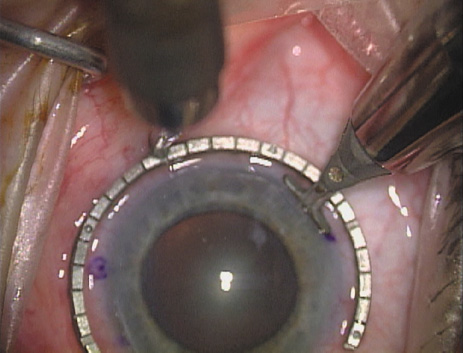

Case 2 is a 79-year-old woman who presented with a very dense left cataract. Her refraction was recorded at −2.25 +2.75 × 125 with a difficult end point. Her manual keratometry and topography measurements were consistent and revealed slightly less than 1.75 D at 120 degrees. Because of the questionable refraction, greater value was placed on the corneal measurements. Based upon the cataract nomogram, the plan was for paired LRIs of 40 degrees to be placed over the steep 120-degree axis (Figs. 1219).

Fig. 12. In this left eye, the steep meridian is at the 120-degree axis and has been delineated by opposing limbal marks. The upper left hand ink mark represents the 6:00 position for orientation. (Reprinted from Hardten DR, Lindstrom RL, Davis EA. Phakic Intraocular Lenses: Principles and Practice. Thorofare, NJ: SLACK Incorporated, 2004, with permission.)